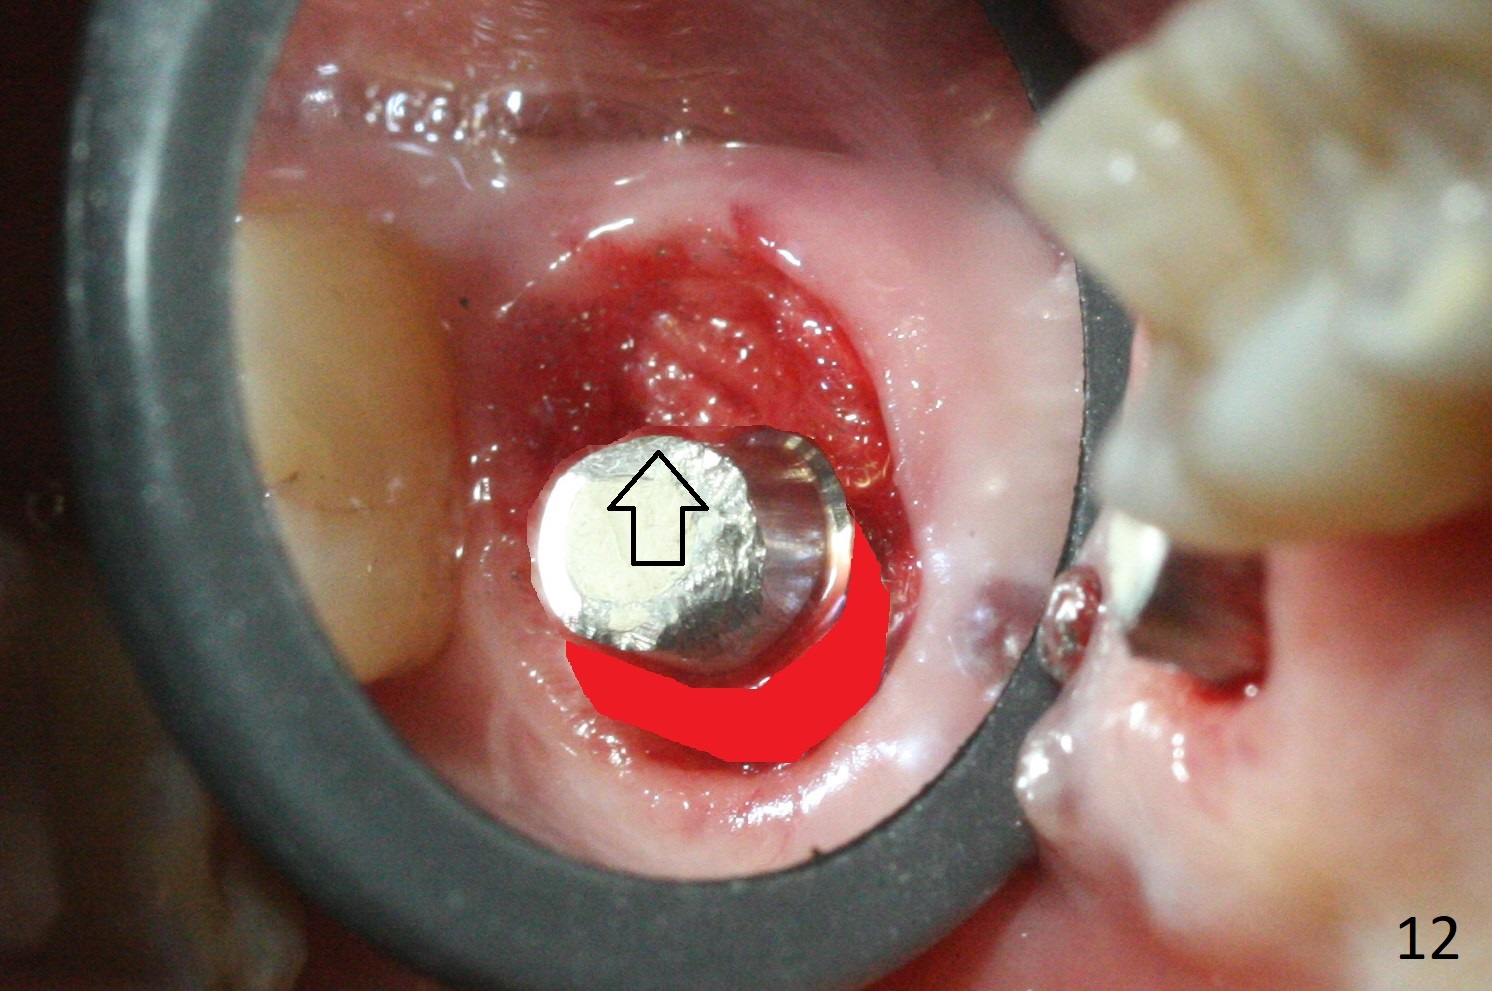

There is a fistula distal to the tooth #2 with deep pocket distopalatally (Fig.1 *), corresponding to palatal root fracture (Fig.2). There is a septum (Fig.3 S) between the buccal (B) and palatal (P) sockets. Osteotomy is initiated in the center of the septum (Fig.4 black circle). In fact the center of the socket is buccal (red circle), in which osteotomy should have been established because of the presence of the distopalatal bony defect associated with the root fracture and the distal fistula. The less ideal initial osteotomy leads to palatal placement of the implant and abutment (Fig.11 vs. 12).

Fig.5 shows the mesial slope of the socket (M), which is more or less the center of the socket mesiodistally. If the osteotomy were set up in the red circle (Fig.6) in the mesial slope (Fig.8 green dashed line), the trajectory of 4.5x11 mm dummy implant (Fig.7) would be more ideal (Fig.8 red outline) with more native bone contact. Finally a longer IBS implant is placed (4.5x15 mm, Fig.9,10) to achieve primary stability (50 Ncm). When the provisional is removed for impression 3 months 10 days postop, the implant is found to have been placed distopalatally (Fig.13), which should have been avoided. It appears essential to use guide for a distal implant. It is agonizing to re-encounter the off-axial implant (Fig.14) and the distopalatal access hole (Fig.15) 1 year post cementation. It is also amazing that the abutment screw has not loosened. A fair-sized piece of bone graft has just been removed buccally (Fig.15,16). The patient complains of sensitivity 2 years 3 months post cementation, although there is no abnormality around the implant crown. Guided surgery is essential to avoid restoration complication. There is no thread exposure nearly 3 years post cementation; in fact the apical portion of the abutment is covered by the bone (Fig.17,18).